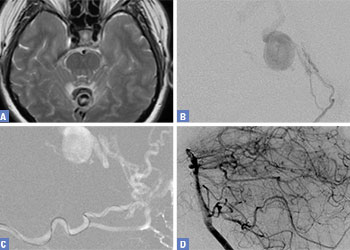

Endovascular:

Hydrocephalus and Brainstem Tumor

Author: Jonathan L. Brisman M.D., F.A.C.S., Read More!